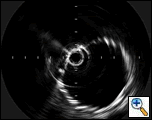

| Figure 3: IVUS showing the site of aortic rupture. |

(Figure 3). The proximal aspect of the transection was 1.5 cm below the origin of the left subclavian artery. Origins of the arch vessels were marked on the masked picture on the fluoroscopy monitor. Using the IVUS, the aortic diameter was measured 28 mm just distal to the left subclavian artery and 29 mm at origin of the left common carotid artery. It was decided to cover the left subclavian artery to get an adequate landing zone for the endoprosthesis. Therefore, the IVUS was placed just distal to the left carotid artery and its position marked on the fluoroscopic screen. The catheter was then withdrawn until above, and then below the transected area. These measured 36 mm and 76 mm in length, respectively. With these measurements in mind, a 30 mm diameter by 130 mm in length Medtronic Talent device with 15 mm proximal wire configuration was selected to exclude the transected portion of the aorta.